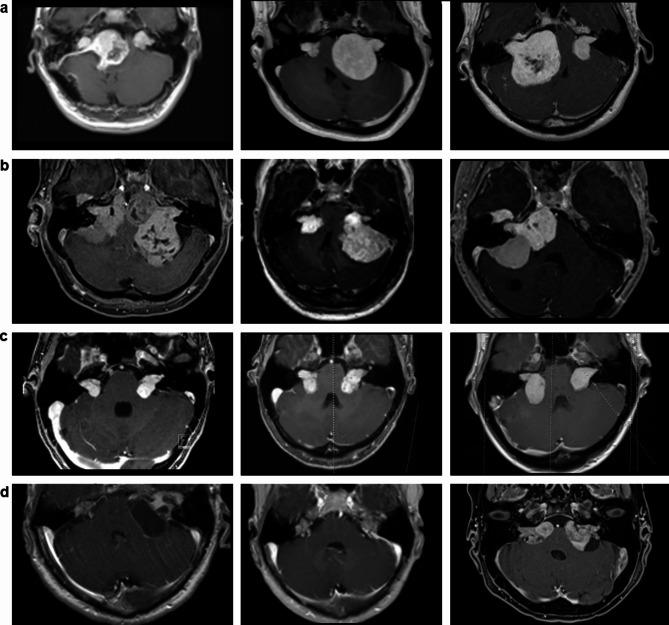

To compare 1D (linear) tumor volume calculations and classification systems with 3D-segmented volumetric analysis (SVA), focusing specifically on their effectiveness in the evaluation and management of NF2-associated vestibular schwannomas (VS). VS were clinically followed every 6 months with cranial, thin-sliced (< 3 mm) MRI. We retrospectively reviewed and used T1-weighted post-contrast enhanced (gadolinium) images for both SVA and linear measurements. 3D-SVA was performed manually or combined with semiautomated segmentation by using axial planes. The maximum linear dimensions (MLD) were determined in three dimensions (anteroposterior, transverse, and craniocaudal planes) using axial and coronal planes. The MLD was cubed (MLD), and orthogonal analysis (OA) was derived to establish comparability with the SVA. The Hannover and Koos classification was used to depict the size ratio in each MRI and tumor. A linear regression model was performed to compare 1D/classification systems to SVA, and the percentage deviation change of MLD and OA to SVA was established using a one-way multivariate variance analysis. 2586 SVA and 10344 linear measurements were performed in a cohort of 149 NF2 patients and 292 associated VS. All measurement techniques (MLD, OA, KOOS, and Hannover) significantly (and strongly, r > 0.5) correlated with SVA (p < 0.001). The OA showed an even stronger positive correlation than the MLD to SVA. Smaller classified tumors (T1/T2, K1/K2) exhibited a low-moderate positive correlation (r = 0.23-0.44) compared to medium-sized (T3, K2/3) and large tumors (T4, K4; r = 0.54-0.76). Pre- and postoperative MLD and OA statistically significantly predict SVA (p < 0.001), but the postoperative correlation was weaker, particularly for MLD to SVA values. All analyses showed a large scatter range. In the percentage deviation analysis of MLD and OA from SVA, small tumors (K1/K2, T1/T2) were overestimated. Compared to the SVA, the MLD and especially the OA are a time-saving alternative for monitoring the tumor volume of NF2-associated VS. However, the scatter range in small/surgically reduced tumors is enormous. For this reason, they are not recommended for monitoring off-label therapy with Bevacizumab or for treatment decisions depending on a precise assessment of tumor volume and growth. Developing deep learning-based volume determinations in the future is essential to reduce SVA's time intensity.

为了将一维(线性)肿瘤体积计算和分类系统与三维分割体积分析(SVA)进行比较,特别关注它们在评估和管理神经纤维瘤病2型(NF2)相关前庭神经鞘瘤(VS)中的有效性。对VS患者每6个月进行一次头颅薄层(<3mm)MRI临床随访。我们回顾性地审查并使用T1加权对比增强(钆)图像进行SVA和线性测量。三维SVA通过轴向平面手动进行或与半自动分割相结合。使用轴向和冠状平面在三个维度(前后、横向和头尾平面)确定最大线性尺寸(MLD)。将MLD进行立方运算(MLD³),并进行正交分析(OA)以建立与SVA的可比性。使用汉诺威和库斯分类来描述每个MRI和肿瘤中的大小比例。进行线性回归模型以比较一维/分类系统与SVA,并使用单向多变量方差分析确定MLD和OA相对于SVA的百分比偏差变化。在149例NF2患者和292个相关VS的队列中进行了2586次SVA和10344次线性测量。所有测量技术(MLD、OA、库斯和汉诺威)与SVA均具有显著(且强,r>0.5)相关性(p<0.001)。OA与SVA的正相关性比MLD更强。与中等大小(T3,K2/3)和大肿瘤(T4,K4;r=0.54-0.76)相比,较小分类的肿瘤(T1/T2,K1/K2)表现出低至中等的正相关性(r=0.23-0.44)。术前和术后的MLD和OA在统计学上显著预测SVA(p<0.001),但术后相关性较弱,尤其是MLD与SVA值之间。所有分析均显示出较大的离散范围。在MLD和OA相对于SVA的百分比偏差分析中,小肿瘤(K1/K2,T1/T2)被高估。与SVA相比,MLD尤其是OA是监测NF2相关VS肿瘤体积的一种省时替代方法。然而,小/手术切除后肿瘤的离散范围非常大。因此,不建议使用它们来监测贝伐单抗的超适应症治疗或根据肿瘤体积和生长的精确评估进行治疗决策。未来开发基于深度学习的体积测定对于降低SVA的时间强度至关重要。